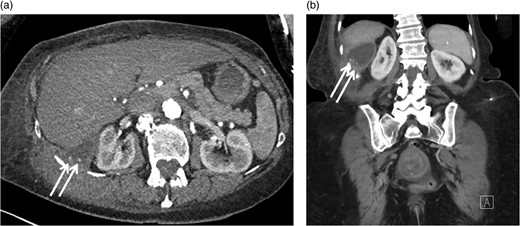

Positron emission tomography-computerized tomography revealed hypermetabolism (Fig. 1d) with maximum Standard Uptake Value of 13.4 g/ml. No overt metastatic spread was identified. The patient was referred for STS multi-disciplinary evaluation including discussion at Sarcoma Tumor Board. Careful review by a musculoskeletal radiologist highlighted the presence of cholecystectomy clips, fascial plane violation and round foci of calcium density (Fig. 3a and b). This raised suspicion for possible retained gallstones, especially since the violation of fascial planes was atypical for STS.

Axial (a) and coronal (b) CT images with IV contrast demonstrating round foci of calcium within the cystic component of the mass involving the right retroperitoneal space.